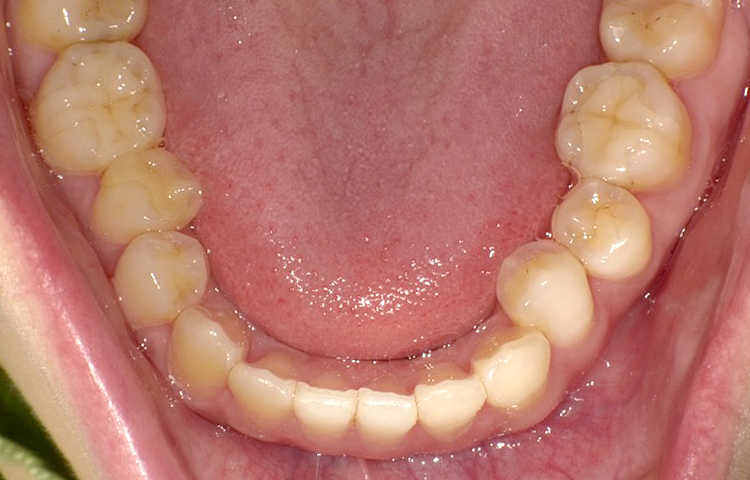

症例6

治療前

治療後

| 主訴 | 右上2番前にでてるのが気になる 上のみ部分矯正希望 |

|---|---|

| 治療 期間 |

約4ヶ月 |

| 治療費 | 247,500円(税込)/調整費用別途 |

| 治療 内容 |

上の前歯部にワイヤーを着けて進めていく、プチ矯正で施術。 |

| 治療の リスク |

奥歯を動かさないので前に出して並べていく。 歯を動かすことで、歯茎が下がるリスクある。 装置による清掃の難しさから、歯肉炎や歯周病、虫歯のリスクが高まる。 矯正終了後は、リテーナーを使用し、後戻りを防ぐ必要がある。 |